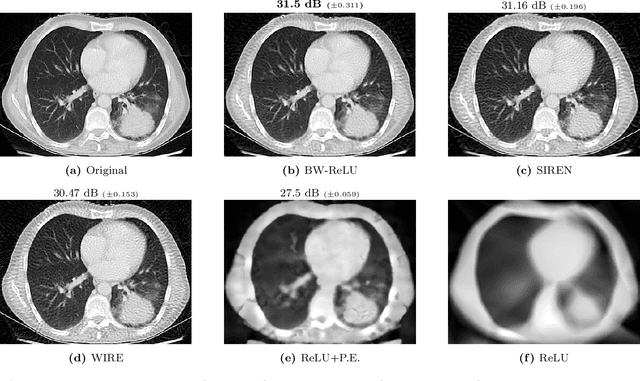

Abstract:Motivated by the growing theoretical understanding of neural networks that employ the Rectified Linear Unit (ReLU) as their activation function, we revisit the use of ReLU activation functions for learning implicit neural representations (INRs). Inspired by second order B-spline wavelets, we incorporate a set of simple constraints to the ReLU neurons in each layer of a deep neural network (DNN) to remedy the spectral bias. This in turn enables its use for various INR tasks. Empirically, we demonstrate that, contrary to popular belief, one can learn state-of-the-art INRs based on a DNN composed of only ReLU neurons. Next, by leveraging recent theoretical works which characterize the kinds of functions ReLU neural networks learn, we provide a way to quantify the regularity of the learned function. This offers a principled approach to selecting the hyperparameters in INR architectures. We substantiate our claims through experiments in signal representation, super resolution, and computed tomography, demonstrating the versatility and effectiveness of our method. The code for all experiments can be found at https://github.com/joeshenouda/relu-inrs.